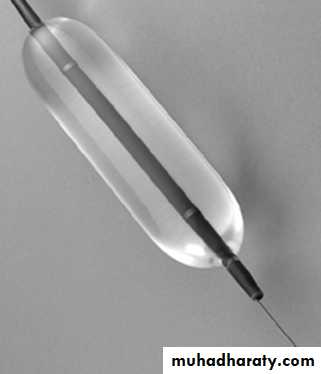

Endoscopic Forceful pneumatic dilatation by using a balloon in lower esophageal sphincter improves symptoms in 80% of patients. Some patients require more than one dilatation. Injection of botulinum toxin into the lower esophageal sphincter induces clinical remission but relapse is common.